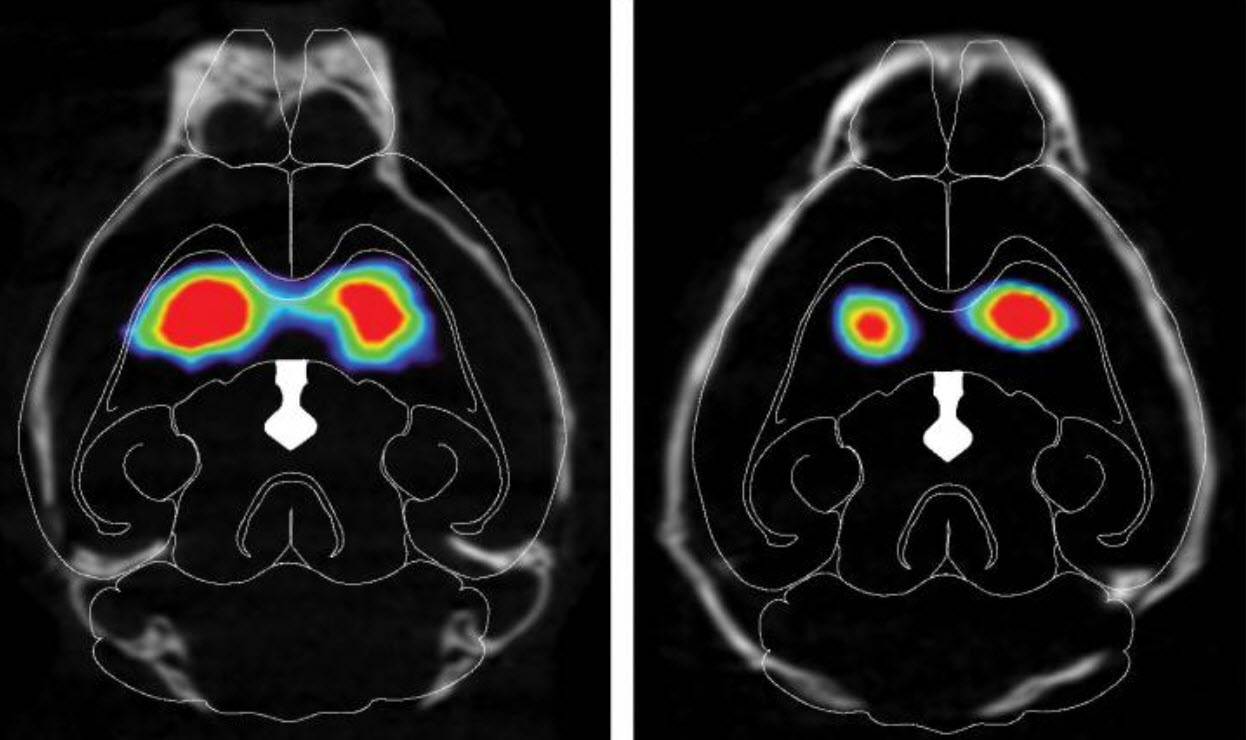

The researchers found that misfolded alpha-synuclein slowly spread to regions of the mouse brain associated with Parkinson's disease, and dopamine-producing neurons started to die. The injected mice performed worse on tests of movement, dexterity, strength, memory, and mental health than mice that hadn't received misfolded alpha-synuclein.

The scientists also found that interfering with the chain reaction caused by the misfolded protein stopped the spread of alpha-synuclein from gut to brain. Mice that had their vagus nerve cut before injection of the misfolded alpha-synuclein into their guts did not have the protein spread to their brains. Mice engineered not to produce any normal alpha-synuclein of their own also had no signs of the misfolded protein in their brains. Both these sets of mice performed similarly on all the tests to mice that didn't receive any misfolded alpha-synuclein.